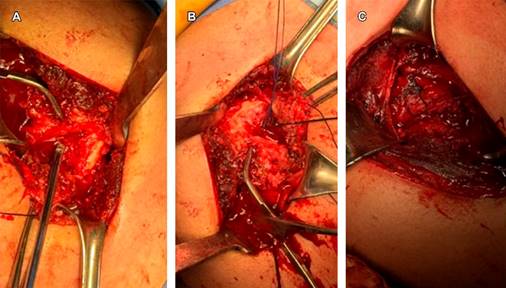

El paciente se posicionó en silla de playa, bajo anestesia general. Se realizó un abordaje deltopectoral, se incidió a través de la cápsula y se redujo la luxación. Se identificó una lesión de McLaughlin de 2 × 3 cm, se limpió el defecto y se colocó un ancla de 3.5 mm con suturas. Se identificó el tendón del subescapular y se realizó la transferencia al defecto con el uso del ancla, siendo reforzado con una sutura transósea de alta resistencia, cubriendo el defecto óseo (Figura 2). Se colocó un inmovilizador universal de hombro.